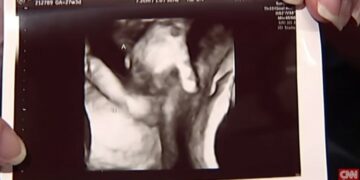

Λίγο καιρό αργότερα έκανε ένα υπερηχογράφημα το οποίο μόλις το είδε έμεινε έκπληκτη.

Στο υπερηχογράφημα διακρίνετε το έμβρυο το οποίο σφίγγει το χέρι της αδελφούλας του.

Η μητέρα φανερά συγκινημένη μίλησε λέγοντας πως επειδή οι πιθανότητες να μην γεννηθεί το δεύτερο μωρό είναι πάρα πολλές, θα κρατήσουν την φωτογραφία γιατί θα είναι κομμάτι που θα τους κρατάει ενωμένους για πάντα και θα τους θυμίζει ότι η αδελφή του του κράταγε το χέρι όταν δεν ήταν κανένας άλλος εκεί γύρο.